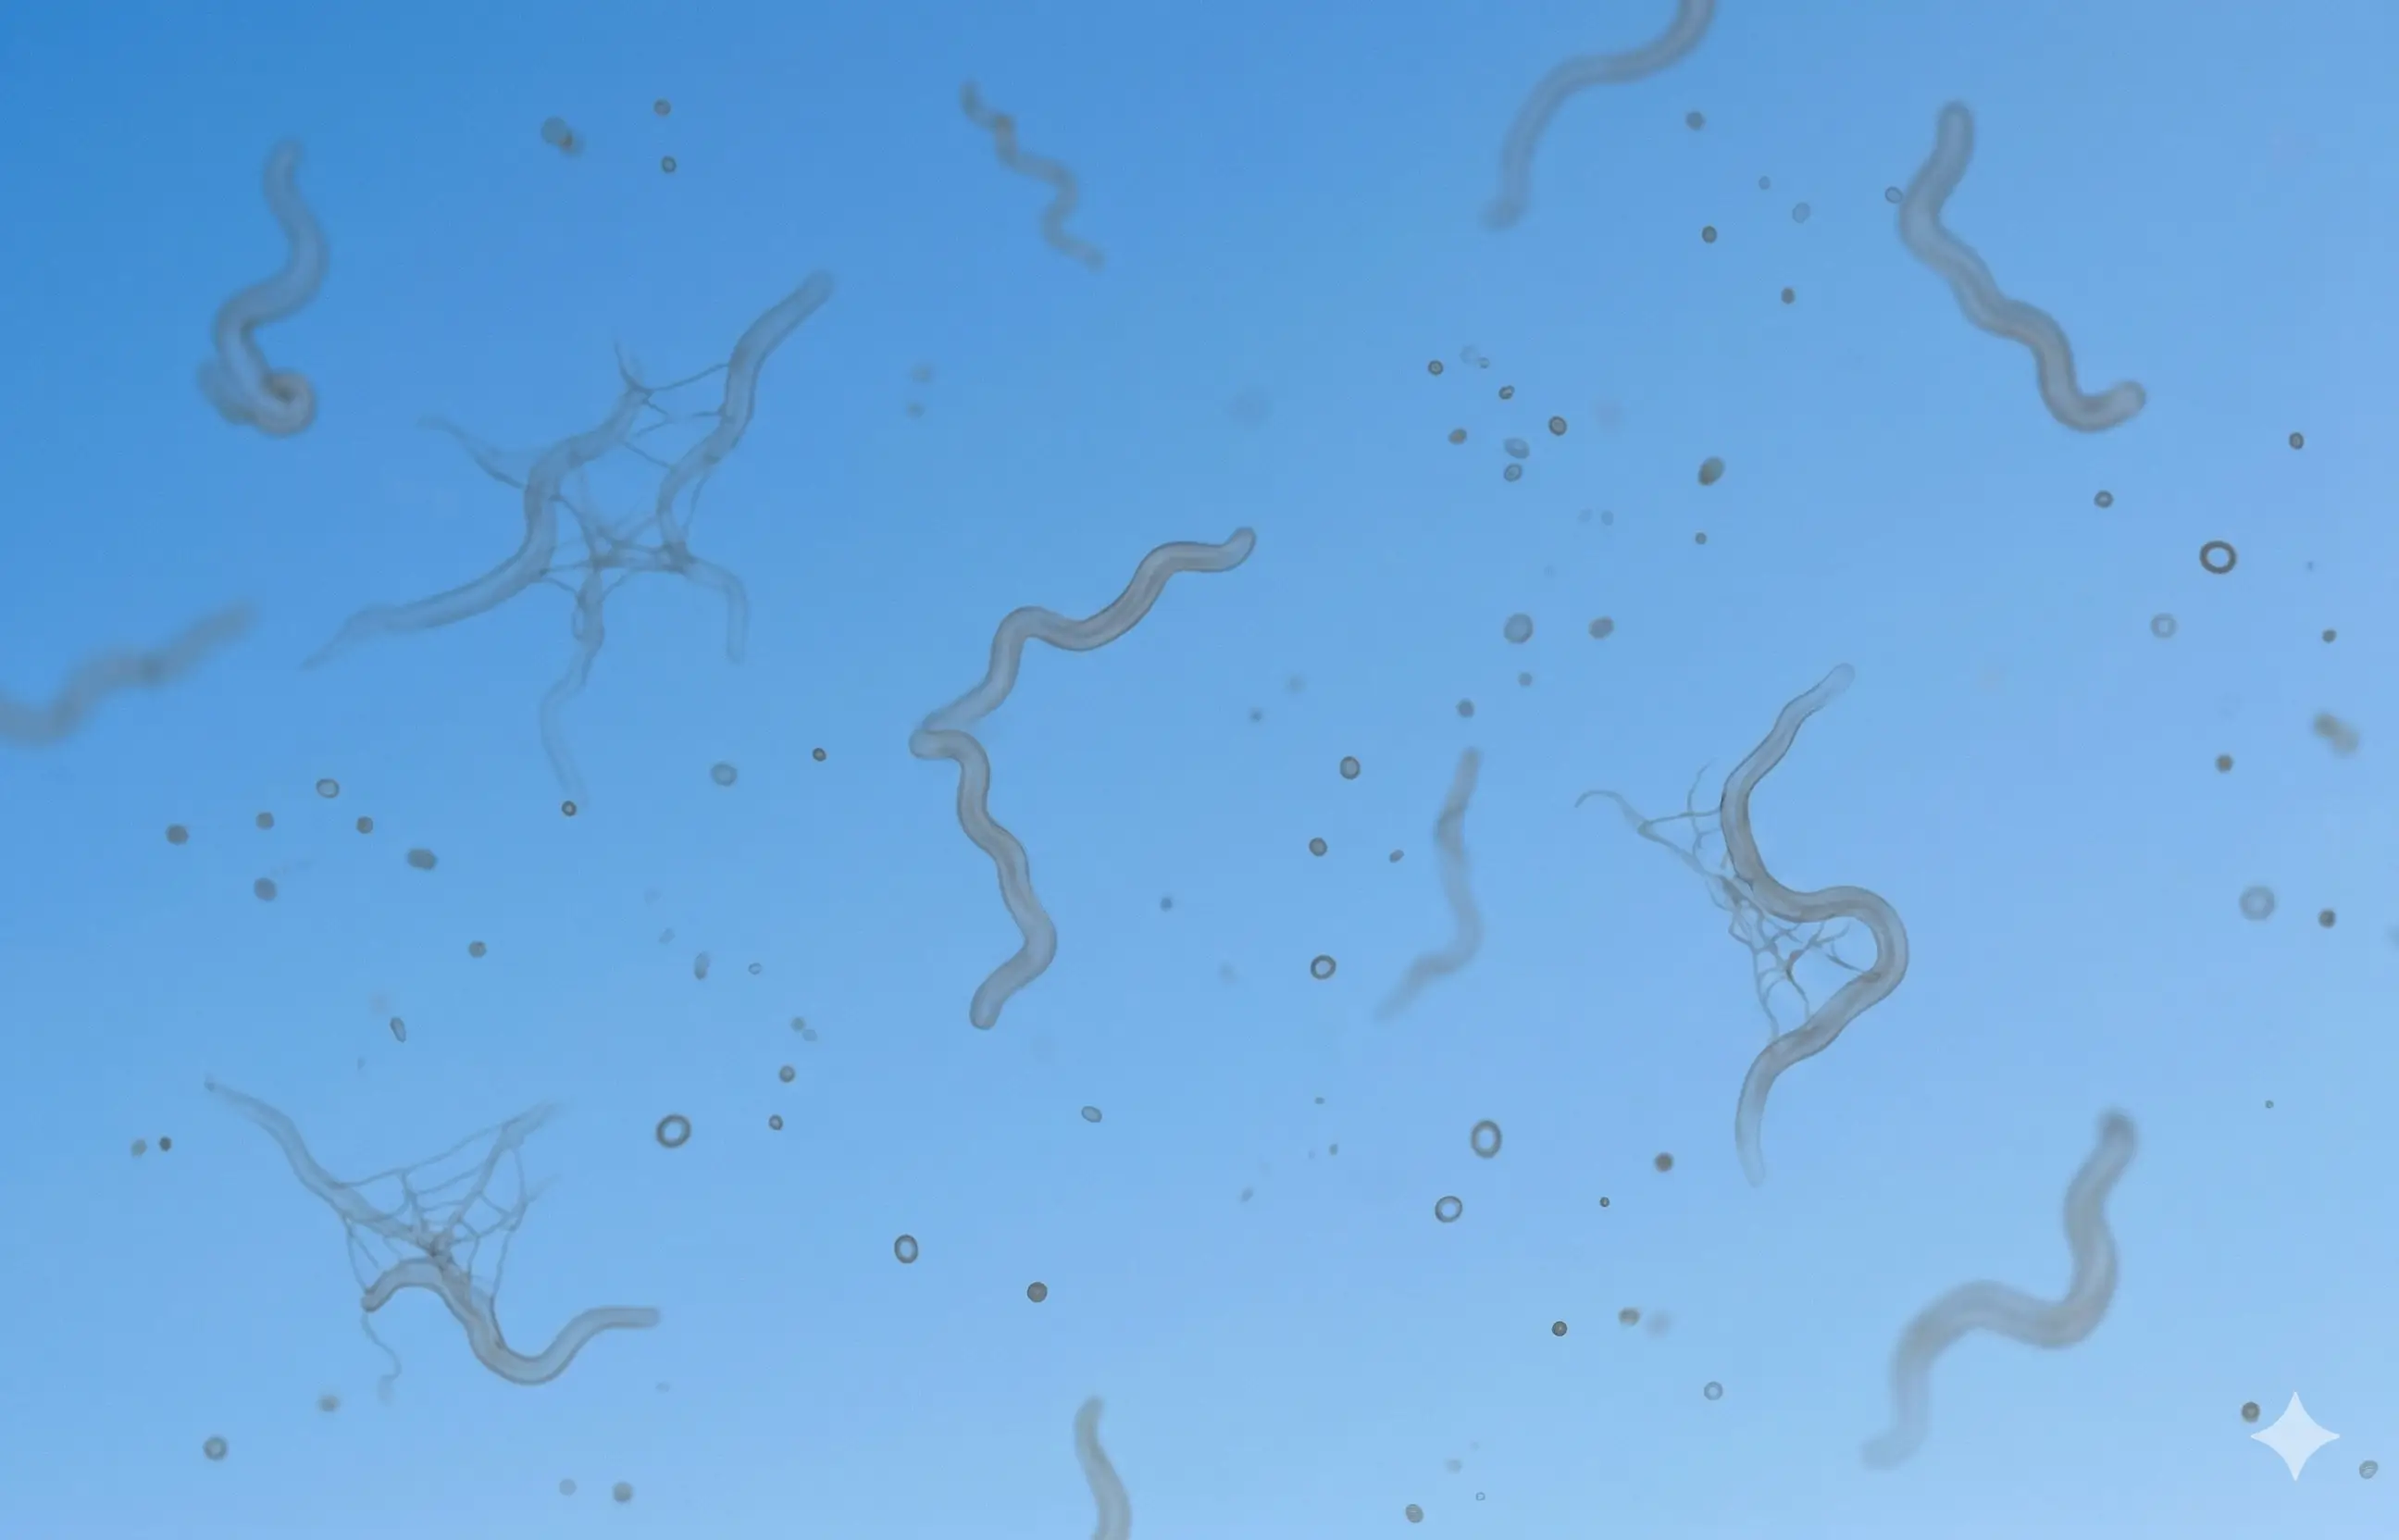

Those dark spots are not just a harmless annoyance. They are a primary early warning sign of progressing retinal damage.